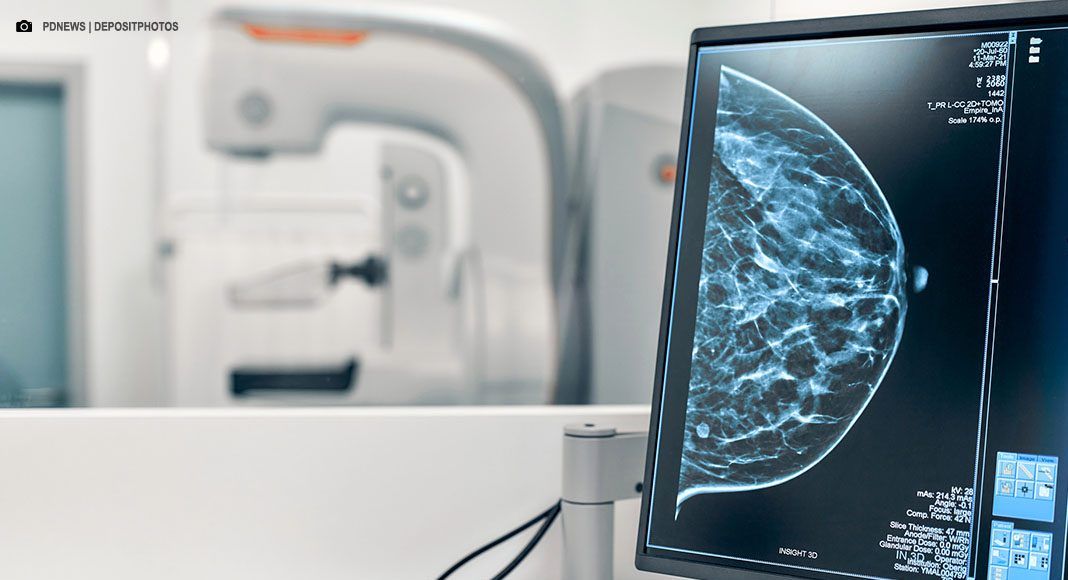

O Governo Federal anunciou nesta terça-feira (23/Set) a ampliação do acesso à mamografia no Sistema Único de Saúde (SUS) para mulheres na faixa de 40 a 49 anos, mesmo sem a apresentação de sinais ou sintomas de câncer. A medida, que busca fortalecer a detecção precoce da doença, permite que o exame seja realizado sob demanda, a partir de uma decisão conjunta entre a paciente e o profissional de saúde.

A iniciativa faz parte de um conjunto de ações anunciadas pelo ministro da Saúde, Alexandre Padilha, para melhorar o diagnóstico e a assistência oncológica no país. Mulheres nessa faixa etária, que concentra 23% dos casos de câncer de mama, enfrentavam dificuldades para realizar o exame na rede pública sem histórico familiar ou sintomas prévios. Em 2024, mamografias em pacientes com menos de 50 anos já representaram 30% do total de mais de 1 milhão de exames.

O governo também anunciou a aquisição de 60 kits de biópsia de alta tecnologia, com investimento de R$ 120 milhões. Os equipamentos, que utilizam imagem 2D e 3D, prometem maior precisão diagnóstica, reduzindo a necessidade de repetição de procedimentos.